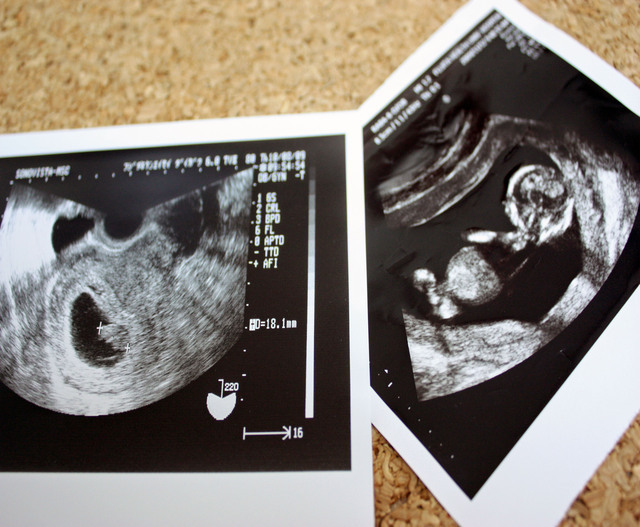

エコー検査でタイミングが良ければ、胎児が体を動かしたり手を握ったりしている姿が見られるかもしれませんよ。この時期になると、胎児も起きている時間と寝ている時間のリズムがついてくるようになります。決まった時間に動いていることも多くなるでしょう。

妊婦健診の感覚も短くなるので、エコーで赤ちゃんの様子をたくさん見ることができてうれしいですよね!ぜひパパも一緒に健診に行ってみてくださいね。